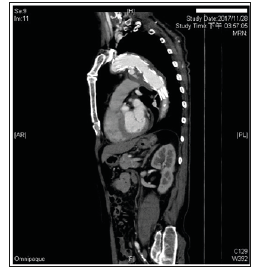

An infected aortic aneurysm combined with SAEF is rare and considered to be one of the most challenging problems faced by cardiovascular surgeons. Conservative treatment of SAEF is not a feasible option because most reported cases result in fatality [2]. The standard treatment of open surgery with resection of the infected aortic segment, extra-anatomic bypass or in situ reconstruction of the aorta, direct suturing for oesophageal repair or oesophageal resection with oesophagogastroplasty or coloplasty, and extensive debridement of the surrounding tissue carries significant morbidity and mortality rates (Figure 1). Operative and in-hospital mortality rates have been reported to be as high as 44% and 57%, respectively, even at experienced centres [3-5]. Thoracic endovascular aortic repair (TEVAR), a less invasive option for patients with this serious condition, was first reported by Semba et al and has become one of the main therapies for thoracoabdominal aortic diseases including thoracic aortic aneurysm (TAA), traumatic aortic transection, and AEF. TEVAR is a minimally invasive alternative to the standard treatment and is especially valuable as a “bridging procedure” in emergency situations [5-6].

Figure 1: Enhanced chest CT examination was performed 3 days after admission to our hospital when the patient’s general condition was stable and confirmed TEVARassociated postoperative SAEF with delayed type Ia endoleak and para-aortic infection.